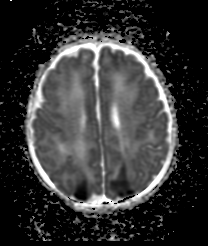

BAMRIThe Birth Asphyxia MRI (BAMRI) project has been ongoing since 1993.  The goal was to see how sensitive MRI was in assessing brain injury of babies who had encephalopathy (abnormal neurological exam, seizures, abnormal blood gases) in the neonatal period.  We saw that brain injury occurred in certain patterns and were able to conclude that those patterns were associated with specific types of injury.  Some types of injuries resulted in damage to areas with high energy demands (brain stem, thalamus, sensorimotor pathways), while others resulted in damage to regions that got less blood flow when blood pressure went down or the heart didn’t contract forcefully.  Some babies had damage to the entire brain, presumably due to a long period with essentially no flow to the brain.  Still others, had very localized areas of injury, which we call a “stroke” or an infarct.  By looking at these patterns of injury and correlating them with outcomes when the babies came back for follow-up neurodevelopmental examinations, our team was able to predict reasonably well what outcome would be based upon the initial MRI.

As time passed, we got additional tools to use on the MRI and more powerful MRIs; these allowed us to do new and better examinations of the babies’ brains.  Proton MR spectroscopy (MRS) allowed us to look at effects of the injury on specific chemicals in the brain.  Diffusion weighted MR imaging (DWI), which looks at water motion in the brain, could show smaller areas of injury at earlier times and could be quantified to see how bad the injury was in different locations.  Even more important, MRS and DWI showed that the injury in the brain rapidly changed over the first few days; it got much worse between day 1 and day 4.  This finding was very important, because it taught us that early intervention might reduce the severity of brain injury.  This discovery led to the trial of therapeutic hypothermia (TH, also called “brain cooling”).  Recent studies have shown that brain cooling significantly reduces brain injury in some newborns, particularly those with injury to the areas with high energy demands when the injury is not very severe.  We think that the babies who do not respond well to TH have a different kind of injury, which has progressed beyond the stage where TH is effective.  Different therapies are now being formulated and will be used in upcoming trials to see if they are effective.